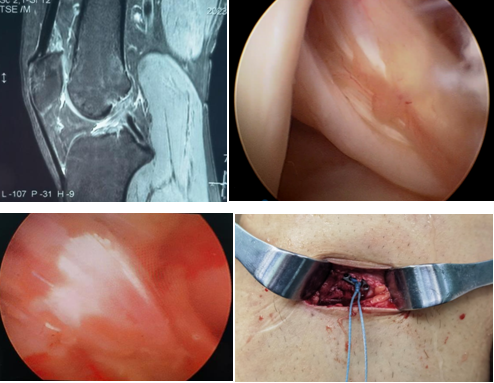

近日,一名31岁男性因打篮球扭伤致“右膝关节疼痛伴行走不稳半年”入院,术前诊断:前交叉韧带部分断裂。考虑患者年轻且有较高的运动恢复需求,在骨科病院刘时璋主任医师的指导下,由冯敏副主任医师主刀完成欧美视频

首例关节镜辅助下前交叉韧带损伤“保残+全内”重建术。患者第二日即下地活动,第三天顺利出院。

ACL的保残重建具有有效促进ACL移植物血管再生,促进损伤ACL本体感觉的恢复,以及防止ACL术后隧道扩大等多种技术优势。而ACL的全内重建技术是国际上新近发展出现的另一项新技术,相比传统方法,它仅需获取自身单根肌腱,而且所需长度远小于传统重建方法。另外,此技术保留了更多的骨皮质及骨膜,术后疼痛更少,腱骨愈合更佳,同时有效降低了术后感染风险,避免了传统方式界面螺钉对肌腱的切割作用。